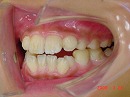

今回の症例写真は治療が比較的困難な 出っ歯<下顎後退症> の改善症例です。

しかし、今回の症例は前回のとは違ったタイプの出っ歯<下顎後退症>です。

初診時 4か月後

横への拡大、縦への拡大、前後の位置の調整をしている事です。